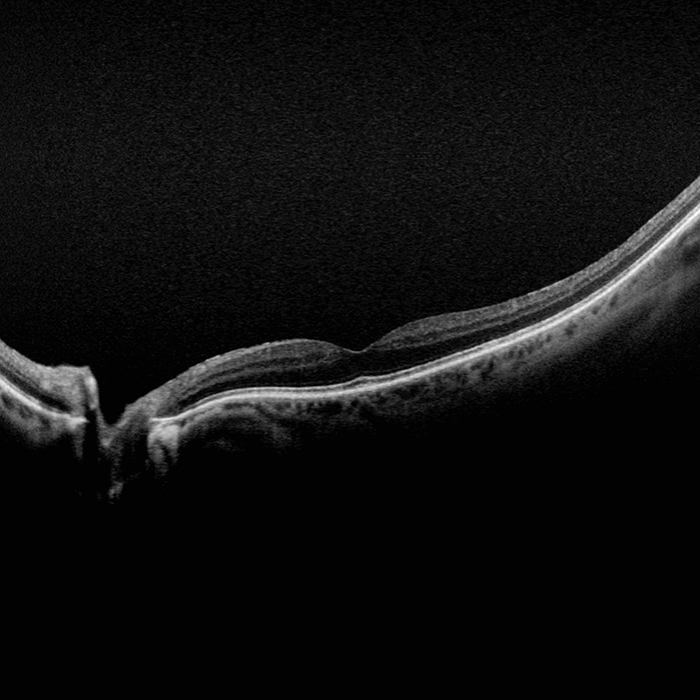

Silverstone est l’outil le plus performant du marché pour l’examen de la rétine. Le seul appareil d’imagerie de la rétine ultra-grand champ avec un OCT Swept-Source intégré, Silverstone produit une image optomap en une seule prise en moins d’½ seconde et permet un balayage par OCT guidé de l’ensemble de la rétine jusque dans la périphérie lointaine.

Il est prouvé que l’optomap améliore la détection des pathologies, la gestion des maladies, et les flux de patients. 1 Grâce à l’OCT Swept-Source intégré, Silverstone facilite l’examen de la rétine, du vitré jusqu’à l’interface choroïdo-sclérale.

- OCT: jusqu'à 23mm lignes de balayage et Swept-Source fonctionnalité